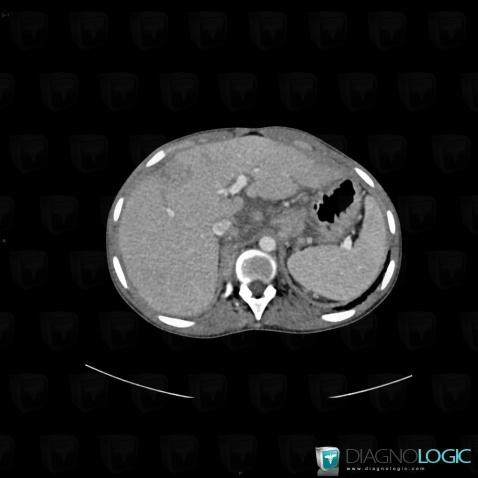

Sarcoïdose, Foie, Scanner

Voici les informations spécifiques à l'image clé ci dessus:

- Diagnostic Sarcoïdose, Localisation(s) Foie, comportant les gammes Hépatomégalie